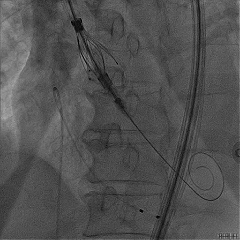

回撤MP导管,一键释放瓣膜

松弯后输送器回撤至大鞘,更换小鞘

术后右窦中心造影,无漏,无AVB